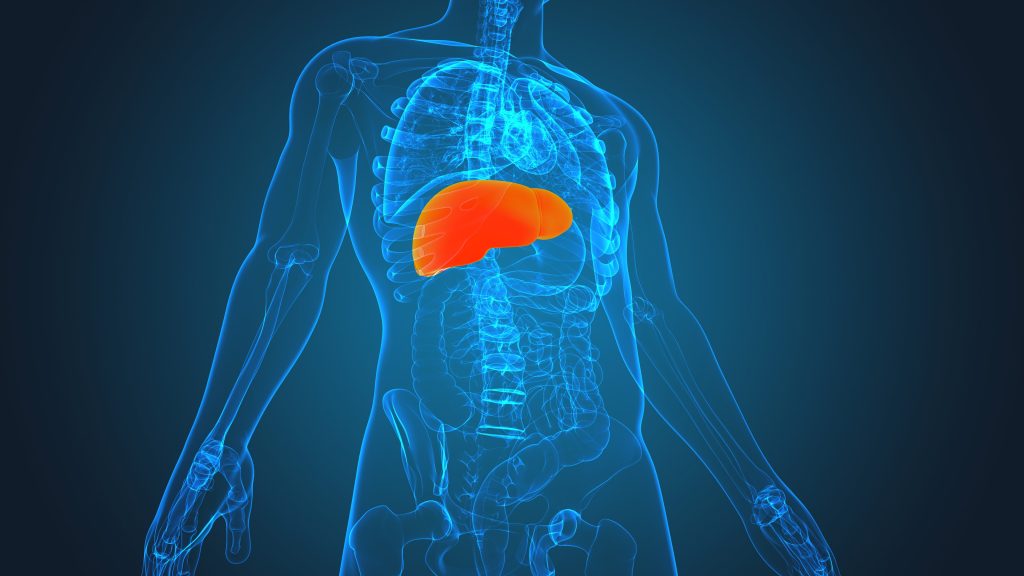

Millions of patients in the U.S. are battling liver disease, waiting for and receiving liver transplants. Early signs of liver damage can most commonly go unnoticed, yet lead to symptoms of liver dysfunction. Some of these are subtle and are missed at times. The Importance of Liver Health Livers. We all have one and know […]

In this webinar hosted by Dr. Meredith Warner discusses everything you need to know about optimizing your liver health. Liver health is a crucial component of overall wellness that often goes overlooked. Our liver performs a multitude of essential functions, from metabolizing nutrients and filtering toxins to aiding in digestion and producing vital proteins. Watch […]

The liver is a vital organ responsible for various metabolic functions such as processing nutrients and detoxifying the body. What we eat directly affects the liver’s ability to carry out these functions, and poor dietary choices can have a serious impact on liver health. Diet Consuming a diet high in saturated fats, added sugars, and […]